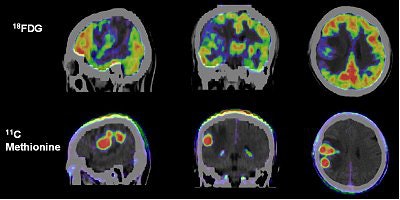

![]() |

Above, T1-weighted postcontrast axial image from the MRI series undergone by Dena Schlosser. Below, an axial diffusion-weighted image. Schlosser's neurologist examined Schlosser after her first trial and, based on the MRI exam, testified that midbrain injuries could cause visual hallucinations. Schlosser had previously told psychiatrists that she believed God wanted her to cut off her child's arms, as well as her own arms, legs, and head (Dallas Morning News, April 3, 2006). Images courtesy of David K. Haynes, Attorney at Law.